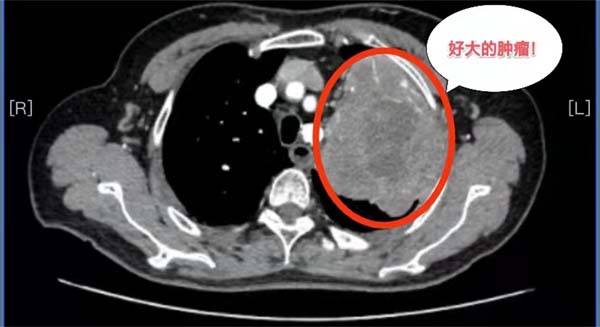

69岁的杨女士在当地医院不幸确诊为局部晚期肺癌,胸部CT检查发现左肺巨大肿瘤,已经侵犯到左肺门、左肺动脉干根部、纵隔及胸壁。当地医院建议杨女士到北京的大医院治疗。此时,患者一家陷入了极度的恐惧与绝望之中。

历经波折后求医无果,经多方打探,抱着最后一线希望杨女士和家人来到应急总医院胸外科求诊。胸外科副主任杨龙海博士从事胸外科专业多年,在肺癌方面具有丰富的诊治经验。杨龙海博士凭借丰富的临床经验,结合外院检查结果,排除远处转移,判断患者有手术的机会,且肺癌根治性手术远期效果相对较好,有治愈的可能。然而,肿瘤发现时已局部晚期,肿块巨大,侵犯到了左肺门大血管,侵犯纵隔及胸壁,加上患者伴有20多年的支气管扩张病史,致使患者症状较重,活动后气喘。这些因素导致手术需要切除整个左肺,手术难度及风险极高,切除过程会遇到肿瘤与肺门、纵隔、心包、胸膜等分离困难的难题,如果处理不当,可能出现大出血、循环呼吸衰竭等严重情况,随时危及生命。